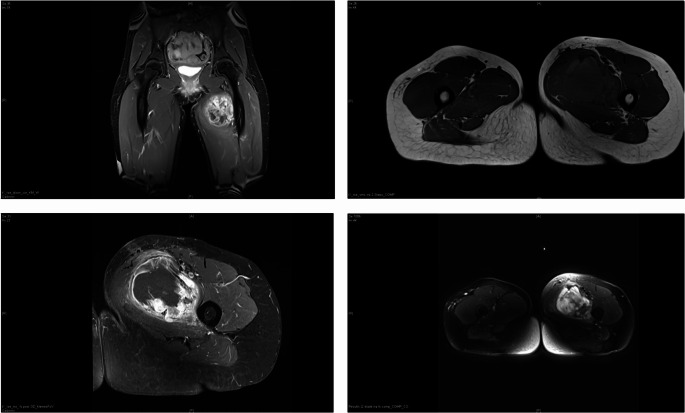

Methods: The questionnaire was developed based on a real case of a 32-year-old female patient with a locally advanced soft tissue sarcoma of the proximal thigh. We invited surgeons who were currently treating patients with extremity sarcomas at German and Swiss sarcoma centers.

Abstract Image